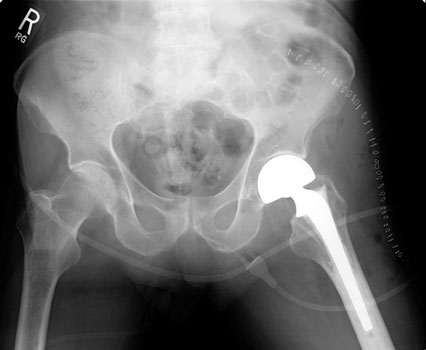

A B

Immediate post operative radiographs after left bipolar hemiarthroplasty (A)  and right total hip arthroplasty (B).